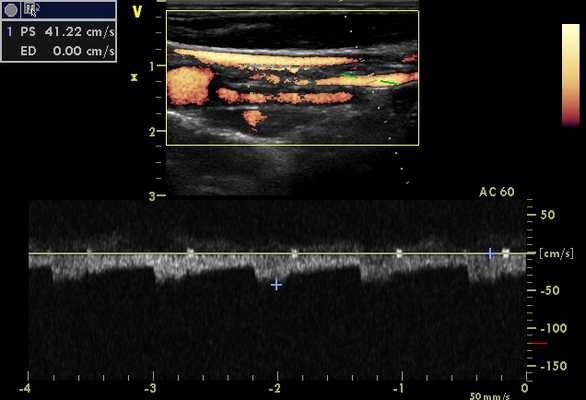

Врач кабинета УЗИ должен быть подготовлен для переключения датчиков, если это необходимо для выполнения обследования сосудов головы и шеи, и крайне важно иметь полное понимание управления техникой для оптимизации изображения и допплеровской информации. Пиковая систолическая скорость, конечная диастолическая скорость, направление кровотока, а также формы допплеровского спектра сигналов должны быть оценены с двух сторон для полного сравнения.

Оценка нормальной подключичной артерии производят многофазный сигнал высокого сопротивления допплеровских сигналов, то есть трехфазный. Цветной допплеровский поток от подключичной артерии будет отражать высокое периферическое сопротивление. Приток крови будет к датчику в пике систолы, а дальше от датчика в начале диастолы и к датчику в конце диастолы. Если возникает значимый стеноз или окклюзия проксимального сегмента сосуда, то допплеровский сигнал дистальнее стеноза будет монофазный. Разница артериального давления на руках более 20 мм рт. ст. обычно связаны с заболеванием подключичной или безымянной артерии на стороне с более низким кровяным давлением.